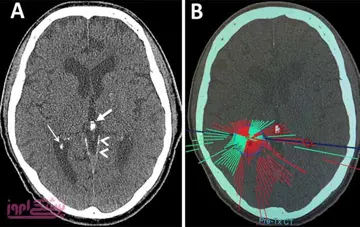

بررسی های جدید حاکی از افزایش کیفیت زندگی بیماران پارکینسونی با کمک پالس های امواج فراصوتی است، که با بهبود چشمگیر و سریع لرزه ها در این بیماری همراه بود .